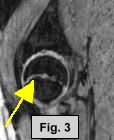

MRI FINDINGS:  The MRI was performed on AIC's high-field 1.5 Tesla short-bore Siemens Symphony.  Coronal T1 and fat suppressed turbo STIR weighted, axial proton density and T2 weighted with Fat Saturation, and sagittal DESS sequences were obtained bilaterally.  Fig. 1 (coronal T1W) shows widening and irregularity of the growth plate in the right hip.  Fig. 2 (coronal STIR) shows subtle adjacent marrow edema and moderate joint effusion.  Fig. 3 (sagittal DESS) and Fig. 4 (axial PD Fat Sat) also demonstrate the same findings.  Subtle medial displacement of the right femoral epiphysis is also noted on the coronal images.